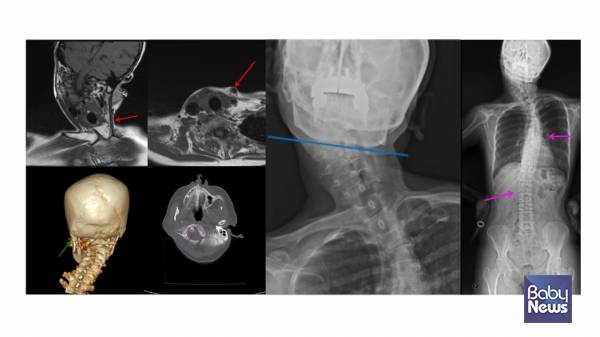

키아리 기형 1형(소뇌가 대후두공 아래로 내려오는 뇌 기형으로, 신경학적 증상을 유발할 수 있음)처럼 소뇌가 대후두공 아래로 내려오는 경우나 뇌종양 같은 중추 신경계 질환도 사경의 원인이 될 수 있습니다. 따라서 근성사경이 아니라는 이유만으로 '자세 문제'나 '습관'으로 단정하기보다는, 필요한 평가를 통해 기저 질환이 없는지를 확인하는 과정이 중요합니다.

치료받지 않은 근성사경은 성장하면서 다양한 2차 문제를 유발할 수 있습니다. 근성사경이 지속되면 얼굴 비대칭, 사두증, 척추측만증, 머리와 목이 만나는 부위의 비대칭까지 이어질 수 있습니다. 성인이 되어서도 목 통증과 자세 이상으로 고생하는 경우를 임상에서 적지 않게 보게 됩니다.

상사시나 안구 진탕(눈동자가 반복적으로 떨리는 상태로, 시야 안정에 영향을 줄 수 있는 증상) 같은 안과적 문제를 확인하는 것이 중요합니다. 또한, 척추 형성의 이상(예 반쪽 척추나 척추 분절 이상)으로 목이 기울어질 수 있습니다.